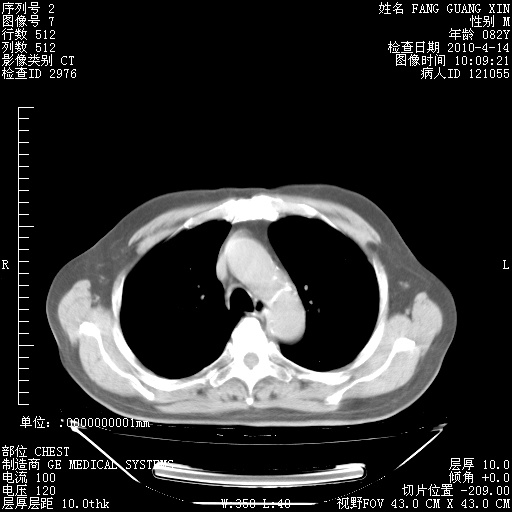

肺部CT平扫未见异常。